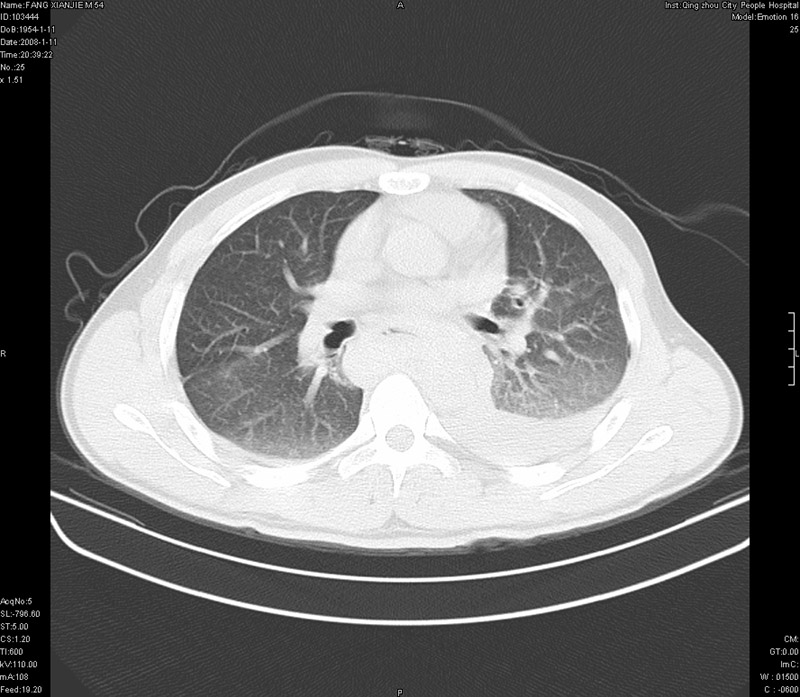

男性,40岁。胸部被车压伤伴胸痛1小时来院就诊。检查:一般情况尚可,血压110/80,胸部及上腹部压痛。结果在三天后公布。骨窗在横断位、冠矢状显示肋骨、胸椎、和胸骨未见骨折征象。

ct11308:胸部外伤1小时(证实病例) (2008-1-13 16:2)结果如下:病人入院后两小时后症状加重,8小时后在征得病人家属同意做了ct增强扫描。如下图。最终临床诊断:外伤性胸主动脉破裂并纵隔内血肿。由于有运动性伪影,胸骨在矢状面重建的图像似有骨折征,这是一种假象,我们称之为“假骨折”,这在多层ct重建中经常性遇到,必要时要结合横断图像鉴别之。现在,病人的一般情况较差,是否要手术家属尚有争议,如果手术修补,难度较大,需要专门预定制作固定支架。

当然,对于该病例,其它非重要的诊断还有:右侧少量气胸;左侧胸腔积液;左侧轻度肺挫裂伤。对于纵隔内血肿,我们曾经遇到过多例,也有怀疑主动脉的破裂,但是,均未得到具体出血部位的明确诊断。